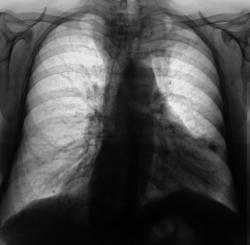

На мой взгляд, слева на верхушке в медиальных отделах верхушеного сегмента (1+2) некоторая динамика есть, да и "кругляк" справа на верхушке (средостении) на 11 срезе, субъективно дифференцируется лучше.

Зоб?

вероятнее всего -зоб, диф. ряд приведен выше

Зоб.